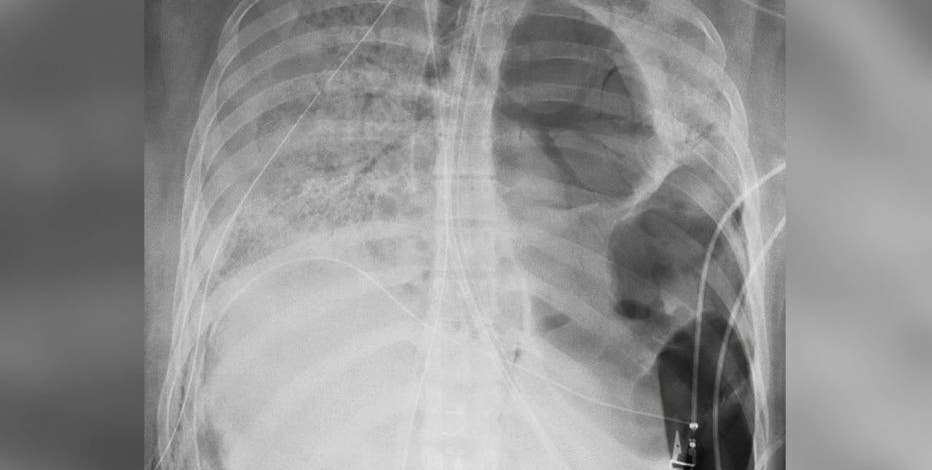

Chest Ct Shows Covid 19 Damage To The Lungs

Coronavirus What X Rays And Ct Scans Reveal About How Covid 19 Kills Science Tech News Sky News